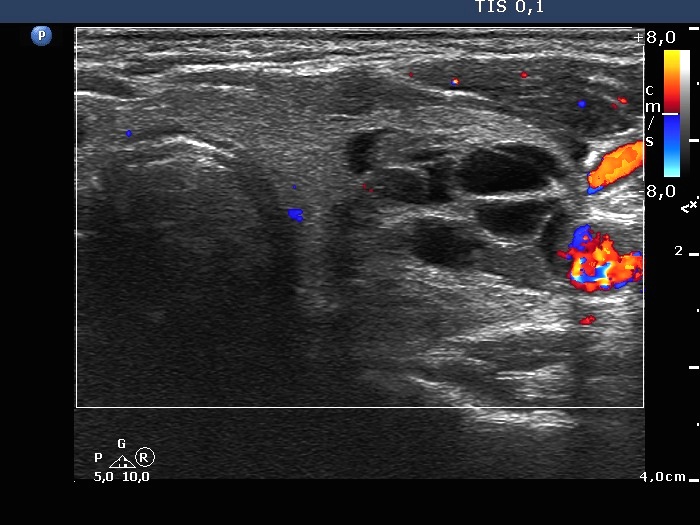

The composition of the nodule - case 142 (ultrasonographic picture 10)

Right lobe, longitudinal scan

Middle-lower part of the left lobe, transverse scan, color Doppler mode. The lesion is avascular.